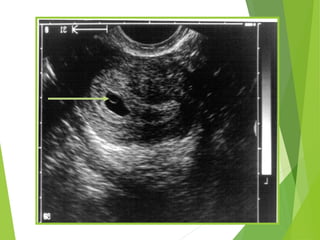

Gestational Sac

 Anechoic area within the uterus surrounded by two

bright echogenic rings

 Decidua vera (the outer ring)

 Decidua capsularis (the inner ring)

 This is referred to as the double decidual sac sign

(DDSS)